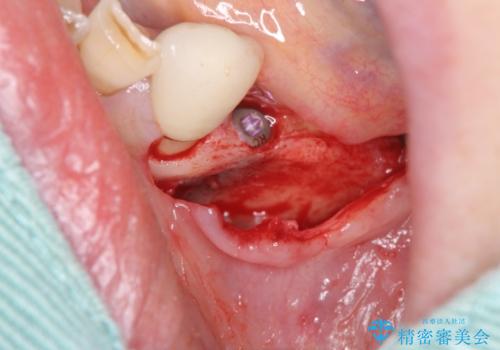

- 歯を失い噛むことができないことを悲観され来院されました。

他院で作製した入れ歯も嘔吐反射により気持ち悪くてはめていることができず、残存した右側の歯の負担は甚大です。

咬合機能を回復し、満足して食事を行えるようインプラント治療を計画します。